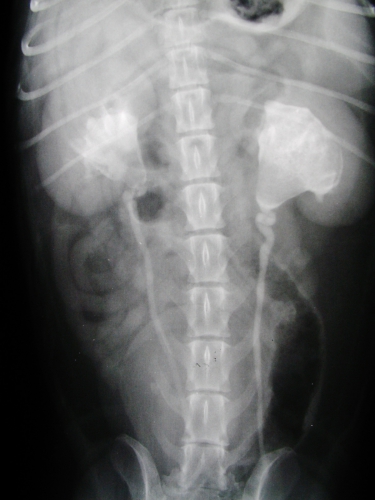

レントゲン検査によって結石の大きさや形、個数、おおよその位置関係を確認することができます。さらに超音波検査によって、結石の正確な位置や周辺の腎盂や尿管内での尿路の拡張や閉塞の有無を確認できます。超音波検査で尿管拡張がみられたり、閉塞が疑われる場合には、静脈性尿路造影が行われることがあります。この検査は静脈から造影剤を注射して、腎臓に集まって、尿管から膀胱へと流れる造影剤の流れの有無やその変化を確認するレントゲン検査です。

レントゲン検査により腎臓や尿管に結石が見つかった場合、さらに超音波検査によって結石の正確な位置関係とそれが周囲に及ぼす影響を評価します。下の2枚の写真は超音波検査の画像です。尿は左から右写真方向に「黒い管」として見える腎盂~尿管の中を流れます。